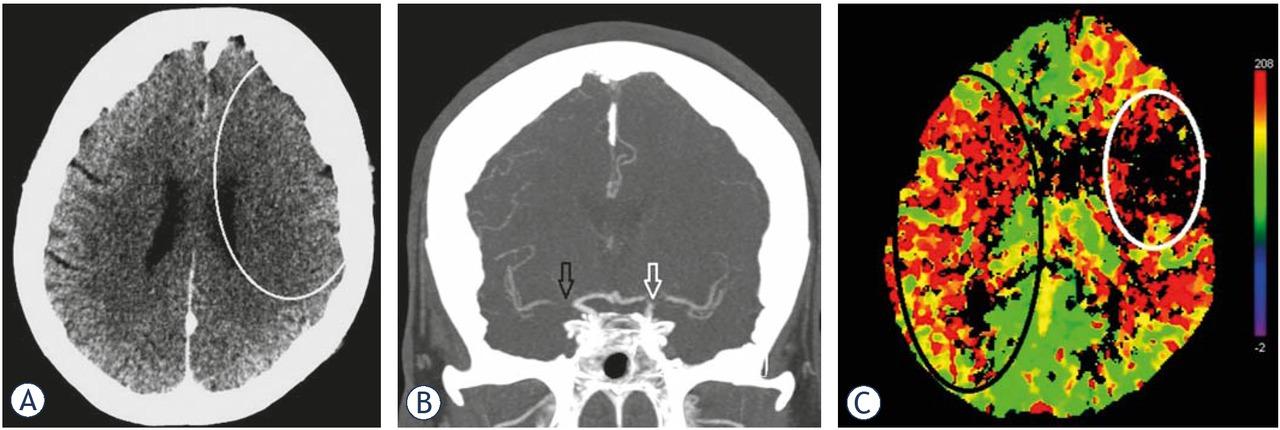

We present a case of a 77-year-old female patient with a medical history of hypertension, diabetes mellitus type 2, hyperlipidaemia and atrial fibrillation who was admitted to the general hospital with an acute onset of left-sided hemiplegia and dysarthria (National Institutes of Health Stroke Scale [NIHSS]: 4, Modified Rankin Scale [mRS]: 3). The patient was last seen without deficits 80 minutes prior to admission. The initial computed tomography (CT) scan revealed no ischaemic brain damage, and CT angiography showed right M1 MCA occlusion (Figure 1). Intravenous thrombolysis (IVT) was administered after 173 minutes and discontinued due to the sudden loss of conscience, the deviation of the head toward the left side and tonic-clonic spasms of the left extremities. The control CT scan performed under general anaesthesia showed no haemorrhagic complications. Since it was assumed that the patient had a symptomatic epileptic seizure, IVT was continued. The sedated patient was immediately transported to a tertiary institution, where a multimodal CT protocol (native CT scan, CT angiography [CTA] and CT perfusion imaging [CTP]) was performed, and the results revealed no signs of ischaemic brain damage in the symptomatic right cerebral hemisphere despite the presence of M1 occlusion and subtle (newly appeared) signs of irreversible brain damage in the contralateral MCA territory due to left ICA (“T”) occlusion. It was obvious that an additional embolic occlusion occurred during the IVT treatment. Although the time of occlusion was long, the CTP imaging results showed a penumbra in the right MCA territory and not in the contralateral left MCA territory, where irreversible brain damage occurred within 3 hours (Figure 2).

(A) Control images taken in the general hospital after clinical deterioration during intravenous thrombolysis and before the transfer to the tertiary institution. There were still no signs of ischaemic brain damage in the right cerebral hemisphere but there were subtle signs of stroke in the left middle cerebral artery (MCA) territory (white line delineates loss of cortical grey matter – white matter differentiation in the frontoparietal lobe with sulcal effacement). (B) Control images taken in the general hospital after clinical deterioration during intravenous thrombolysis and before the transfer. CT angiography (CTA) showed persistent right M1 occlusion (black arrow) but also left carotid “T” occlusion (white arrow). (C) Control images taken in the general hospital after clinical deterioration during intravenous thrombolysis and before the transfer. CT perfusion imaging (CTP) showed a penumbra in the right MCA territory (black circle) and irreversible brain damage in the left MCA territory (white circle).